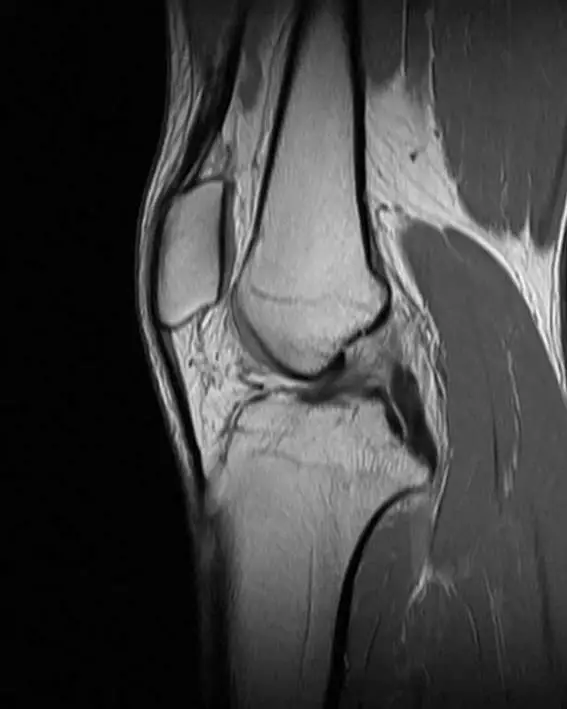

MRI 矢狀面 T2 fat-sat 加重像

ACL 呈現纖維中斷、不連續,近端纖維信號增高,遠端過度彎曲 (buckling),為 ACL 完全撕裂的典型影像學徵象 (pmc.ncbi.nlm.nih.gov)。 -